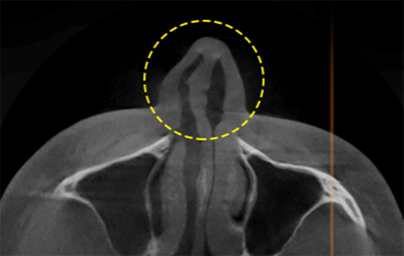

透過立體的骨骼圖進行精準診斷的 3D CT